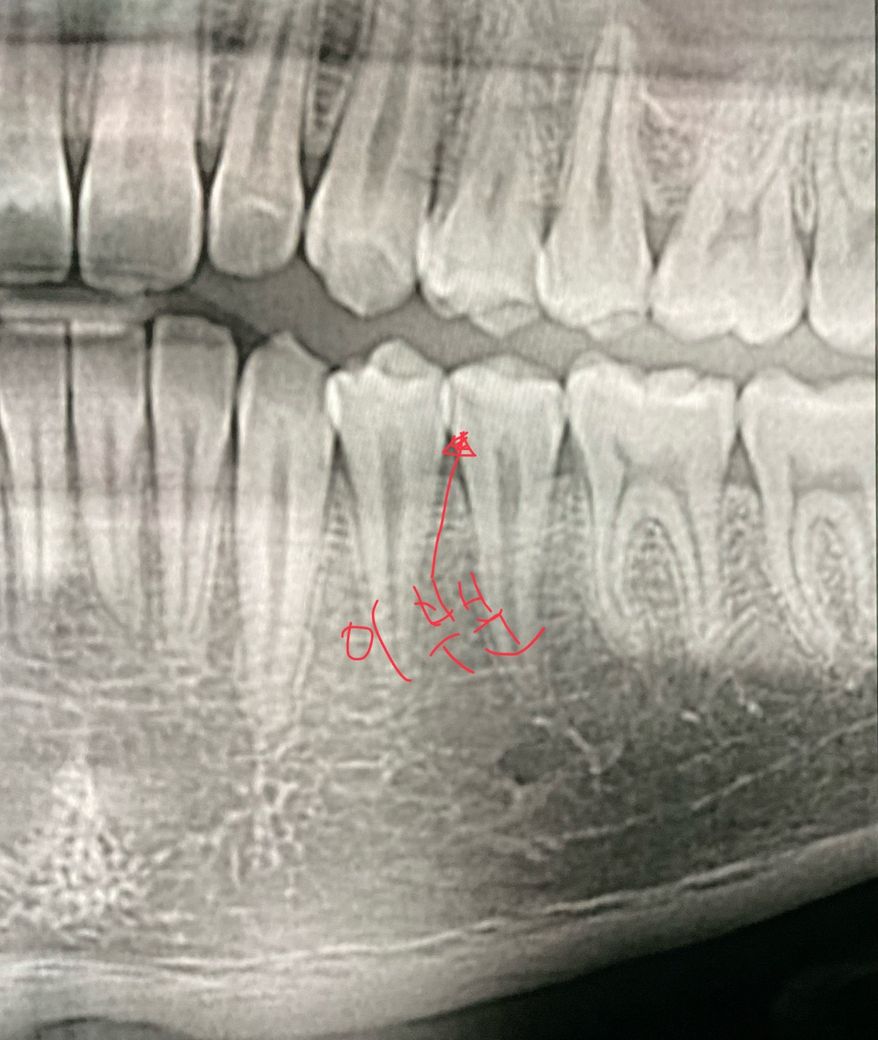

이게 신경치료하고 크라운까지 할 치료였는지 궁금해요.. 차라리 아팠을때 했으면 이런 의심도 안했을텐데 안아팠을때 하니ㅠ 스트레스네요 ㅠㅠ 다른 사진이 있긴한데 그건 없고 충치 치료한 사진 보여주는데 카운터에서 이게 신경이라고 보여주더라고요 불가피 했던건지 ㅠ

엑스레이 사진 중에 이거보다 작은사진(치근단사진)이 있어야 판단이 가능합니다 위사진으로는 신경치료가 필요할정도로 큰 충치는 없어보입니다

큰 엑스레이 사진으로는 판단이 어렵고 작은 사진이 잇다면 더 정확히 판단할수 잇지만, 저 사진으로는 충치가 많이 깊어 보이진 않습니다.

해당 사진보단 치근단사진이라고 하는 사진이 더 정확하지만 증상이 없다면 인레이 했을 것 같습니다.